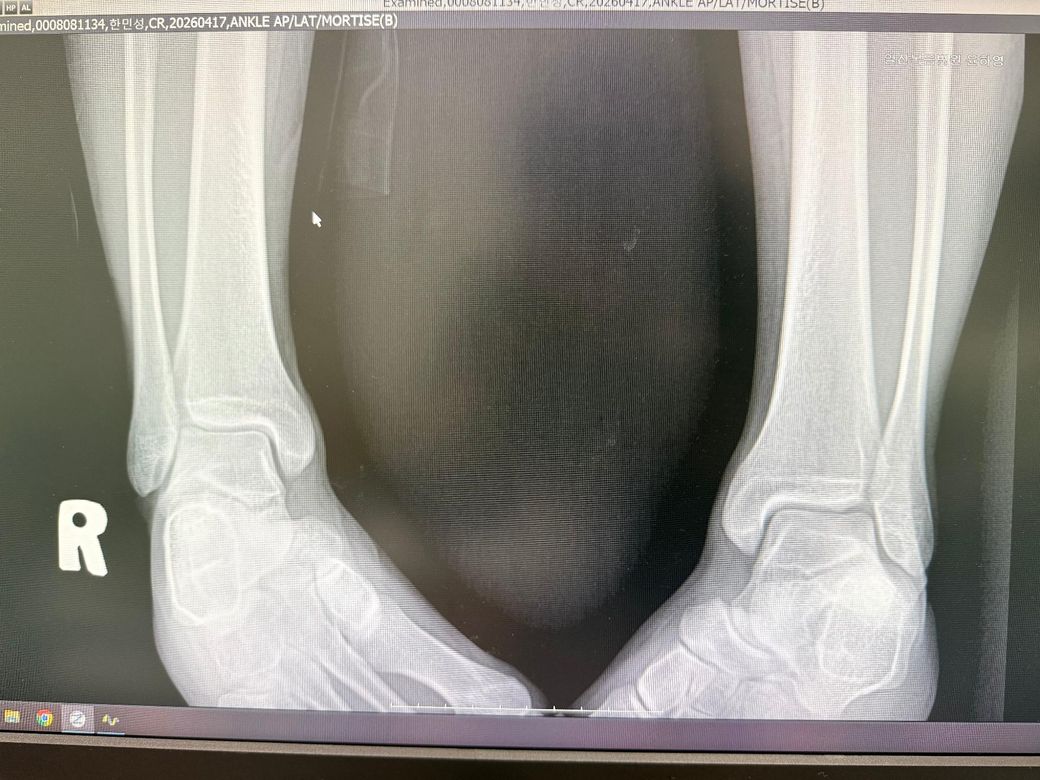

뼈에는 당연히 문제가 없고

문제는 뼈 안쪽을 잡아주는 인대가 약간 끊어졌다고 하시더군요

1. 엑스레이만 봤을때 몇도, 몇단계 염좌가 의심될까요? 2도 염좌를 넘을 가능성이 있나요?

• 1번 째 사진

• 2번 째 사진

그리 심각한 부상은 아닐 것으로 생각되며 엑스레이만으로 몇 도 염좌 판단은 정확히는 불가능하며 인대 상태 확인을 위해서는 초음파나 MRI검사를 받아보시는게 좋기는 합니다.

• 사진과 경과를 종합하면 전형적인 외측 발목 염좌 양상으로 보이며, X-ray상 골절 소견은 없어 보입니다. 현재 설명하신 “걸을 수는 있으나 불안정감과 약간의 뻣뻣함” 정도라면 임상적으로는 1도에서 2도 사이, 즉 부분 파열 수준의 염좌 가능성이 높습니다. 완전 파열(3도)에서는 보행이 어렵고 압통이 뚜렷하며 부종이 심한 경우가 많아 현재 상태와는 거리가 있습니다. 다만 X-ray는 인대를 평가하지 못하므로 정확한 등급 판정은 진찰 소견이나 필요 시 초음파, MRI로만 가능합니다.